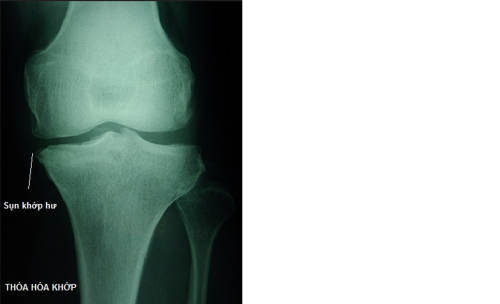

- Thoái hóa khớp: Là quá trình thoái hóa tự nhiên của sụn khớp do tuổi tác, chấn thương hoặc sử dụng quá mức. Biểu hiện chính của bệnh là đau và cứng khớp, thường gặp ở các khớp chịu lực như khớp gối, khớp hông và cột sống.

- X-quang: Giúp quan sát cấu trúc xương và khớp, phát hiện các tổn thương như thoái hóa khớp, gãy xương và lệch khớp. X-quang thường là phương pháp chẩn đoán đầu tiên được sử dụng khi nghi ngờ có vấn đề về cơ xương khớp.